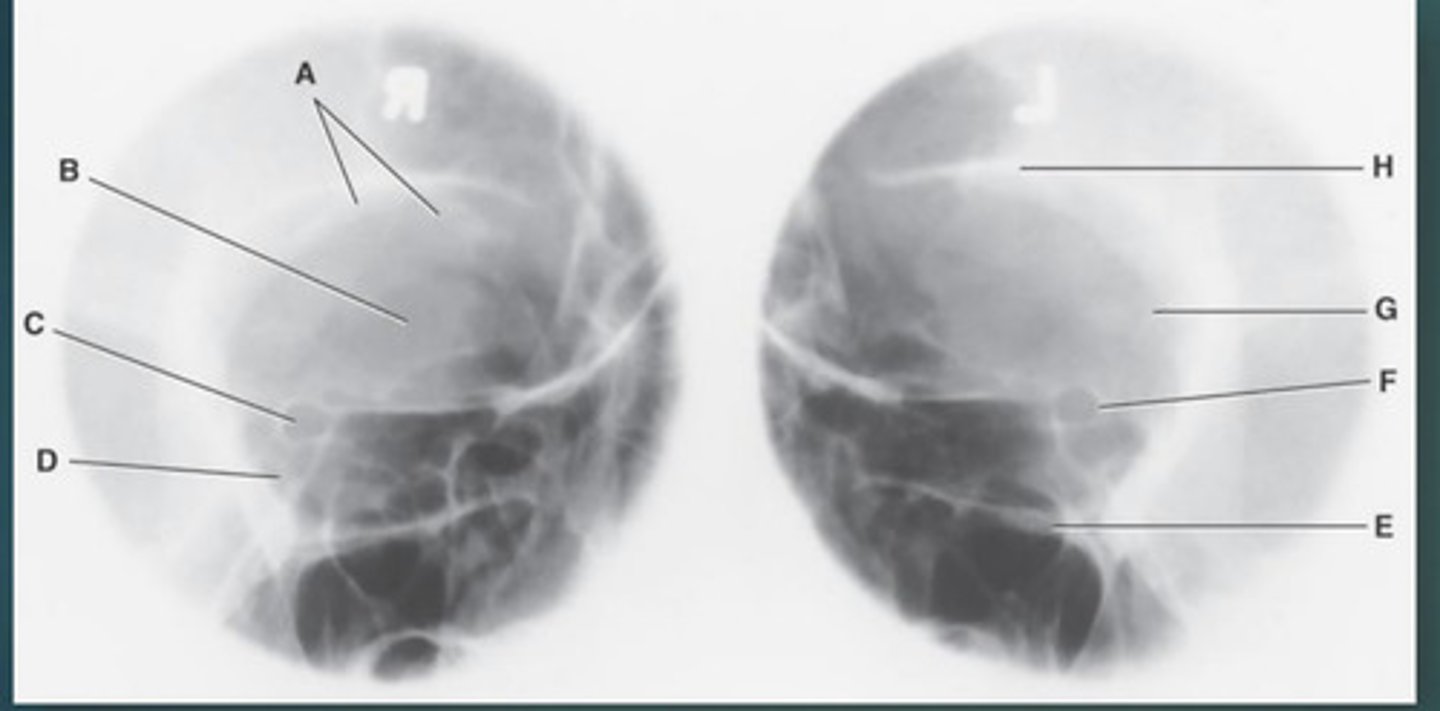

Lateral sinus

What position?

L. Orbital roofs

A.

L. Greater wings of sphenoid

B.

sella turcica of sphenoid

C.

L. Sphenoid sinus

D.

L. Rami of mandible

E.

L. Maxillary sinuses

F.

L. Ethmoid sinuses

G.

L. Frontal sinuses of frontal bone

H.